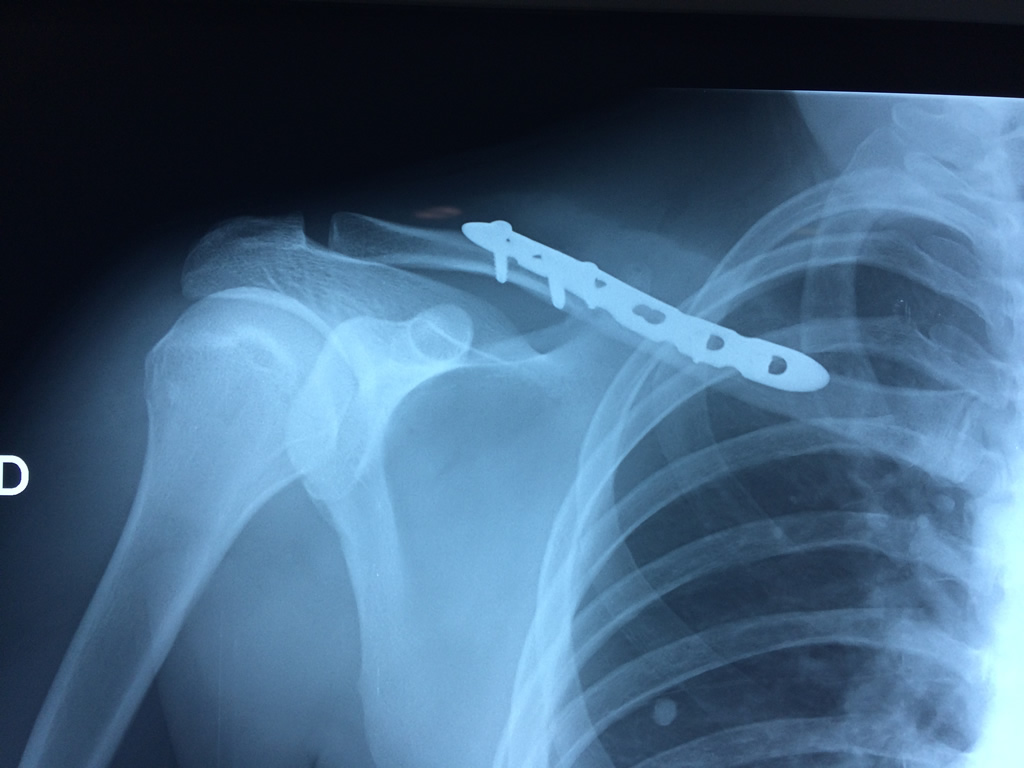

Cirugías de Hombros - Clavícula